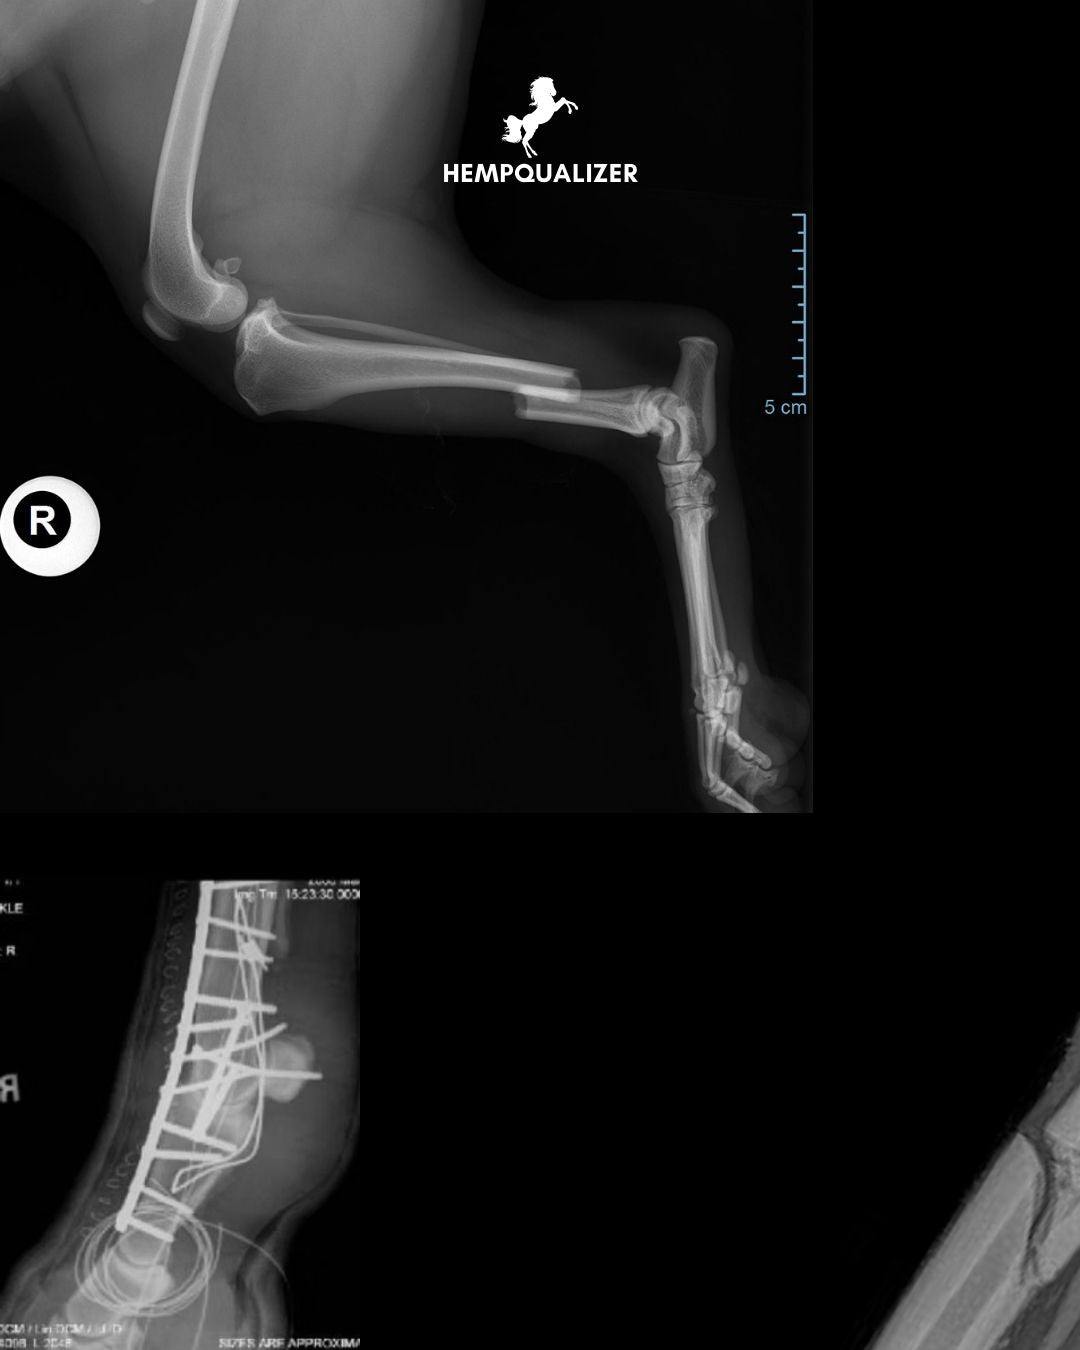

8. Repair? Extremely Challenging

The bones are thin, and the forces are immense. Screws and plates must withstand up to 150 kg of weight per leg, yet they often loosen, become infected, or fail due to fragment shifting. Successful treatment demands the highest level of surgical skill—and still, success is not guaranteed.

An adult horse weighs between 500–600 kg, and all of that mass is supported by four slender legs. For example, the cannon bone (metacarpal/metatarsal) measures only about 2.5–3 cm in diameter. Trying to bear weight on a fractured limb often leads to severe tissue damage and complications.

Below the carpal joint (front legs) and hock (hind legs), there are no muscles—only bones, tendons, and ligaments. This means the bones are unprotected and unstabilized. Fractures quickly become open wounds, greatly increasing the risk of infection.